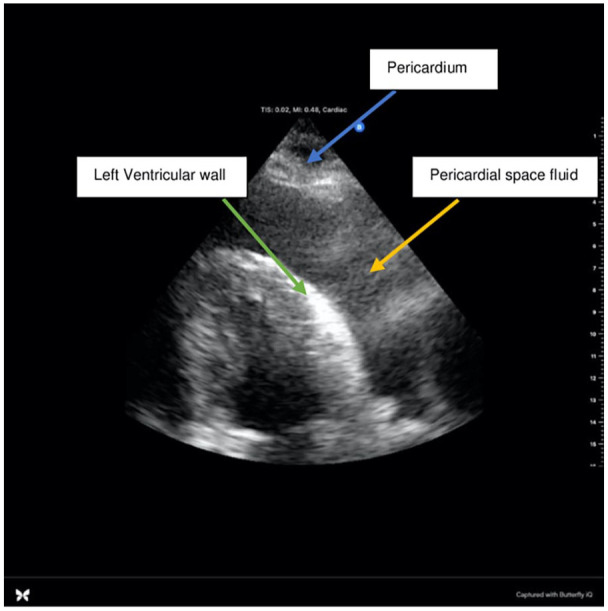

Pericardial effusions, though relatively rare, can lead to life-threatening complications such as cardiac tamponade. While viral etiologies are common culprits, rapid and accurate diagnosis remains challenging. We present the case of a 74-year-old male with a history of upper respiratory infection who developed sudden onset dyspnea and chest discomfort. Bedside point-of-care ultrasound (POCUS) revealed a large pericardial effusion, prompting urgent intervention. Despite initially stable vital signs, the patient rapidly deteriorated, necessitating emergent pericardiocentesis. Laboratory findings and pathology results eventually ruled out common viral causes, guiding diagnosis toward coxsackieviruses A and B, echovirus, adenoviruses, or influenza. This case highlights the critical role of POCUS in resident-led community hospitals, in expediting the diagnosis of pericardial effusions and underscores the need for prompt intervention in cases of cardiac tamponade to prevent adverse outcomes.